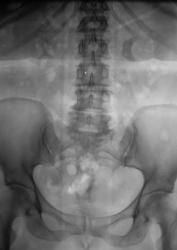

Пол пациента: Мужской пол Тип патологии: Другое Область исследования: Мочеполовая система Методы исследования: Rg Пациент направлен в рентгеновский кабинет для производства внутривенной урографии с подозрением на опухоль левой почки. Произведено стандартное исследование. Ваше мнение коллеги? Вс, 24/05/2009 - 21:05 #1 Андрей Юрьевич Не на сайте Был на сайте: 1 неделя 4 дня назад Зарегистрирован: 16.11.2008 - 22:16 Публикации: 18098 Такой можно и коралловидным назвать. Андрей Юрьевич Пнд, 25/05/2009 - 10:47 #2 v1tal Не на сайте Был на сайте: 4 года 9 месяцев назад Зарегистрирован: 07.06.2008 - 19:41 Публикации: 1779 А сколько лет пациенту? В анамнезе туберкулеза нет? "Знаешь, у некоторых врачей есть комплекс мессии — им необходимо спасать мир. А у тебя комплекс Рубика — тебе необходимо решать головоломки." Пнд, 25/05/2009 - 15:45 #3 Катенёв Валенти... Не на сайте Был на сайте: 7 лет 3 недели назад Зарегистрирован: 22.03.2008 - 22:15 Публикации: 54876 В анамнезе туберкулёза (легочного) нет. Пациенту 42 года. Мочу, сейчас, у всех пациентов с "урологической патологией" на МБТ и "смотрят и сеют". А какое мнение коллег по поводу правой почки?

Такой можно и коралловидным назвать.

В анамнезе туберкулёза (легочного) нет. Пациенту 42 года. Мочу, сейчас, у всех пациентов с "урологической патологией" на МБТ и "смотрят и сеют".

А какое мнение коллег по поводу правой почки?